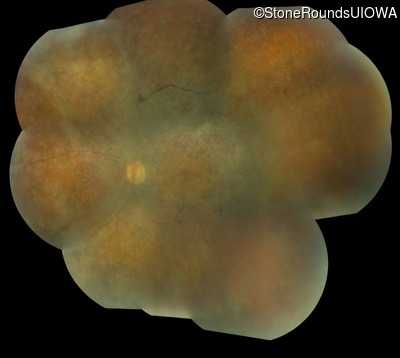

AD Retinitis Pigmentosa (IA1aii)

Age at visit: 53 years

This 53 year old woman first came to attention when she had difficulty walking down stairs. A few years later she noticed difficulty seeing in dim light.

Diagnosis & molecular findings

AD Retinitis Pigmentosa PRPH2 Pro216Ser CCT>TCT   AD